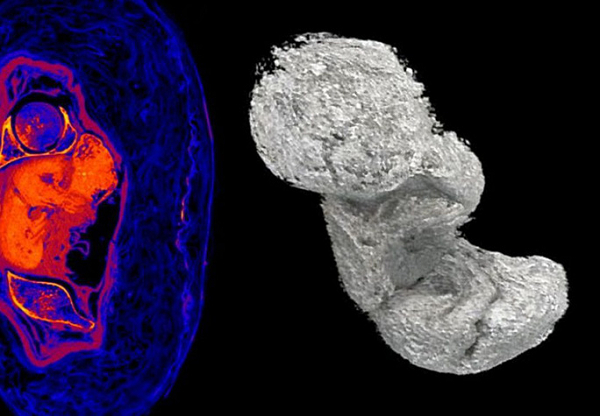

Xác ướp bí ẩn từng bị lầm tưởng là của linh mục Hor-Djehuti cho đến khi kết quả kiểm tra vào năm 2016 cho thấy đó là một phụ nữ. Sau đó vài năm, kết quả quét CT đã gây choáng váng khi người ta phát hiện một bào thai 26-30 tuần tuổi trong bụng cô.

Toàn bộ cơ thể thai nhi trải qua quá trình khoáng hóa, y như cách người Ai Cập đã cố tạo nên cho các mô của xác ướp người lớn. Đó là lý do trong ảnh chụp CT, thai nhi hầu như không thấy xương cho dù hình hài thì rất nguyên vẹn.